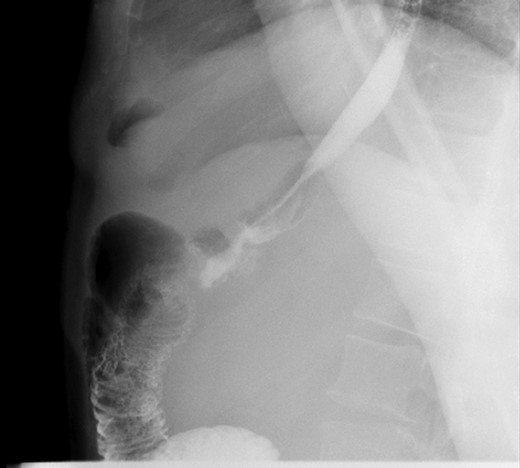

Second patient is a 35-year-old female with BMI 32.3 of with history of diabetes mellitus, hyperlipidemia who underwent LRYGB in June 2014, laparoscopic cholecystectomy 2014 was seen in the clinic for 1 year follow up. After having lost 54 pounds with right sided abdominal pain associated with nausea and vomiting. Patient had an upper GI which was negative and subsequently still continue to have the abdominal pain and undergone an EGD which was normal as well. At that point patient was lost to follow up for over a year as she moved to Florida and states while in Florida had CT scan of abdomen which showed questionable internal hernia at the anastomosis. Patient was seen and evaluated in our emergency room with complaints of right sided abdominal pain with nausea and vomiting. Vital signs were stable. On physical exam, tenderness in the epigastric area. All the labs findings were unremarkable. CT scan of abdomen did not show any abnormality. However, due to possibility for an internal hernia, patient was admitted and was taken to the operating room for diagnostic laparoscopy on November 2017. She was found to have long candy cane limb. We resected excessive redundant 4 cm length of the long blind jejunal loop of gastrojejunostomy anastomosis using Endo GIA Tri-Stapler device, Intra-op EGD was performed showing 4 cm gastric pouch. Post-operative course was uneventful. The patient was discharged to home on post-operative Day 4 and returned to clinic 1 week for follow up and tolerating diet and completely asymptomatic and pain free. Three weeks post laparoscopy patient had upper GI which was found to be normal (Figs 3 and 4).